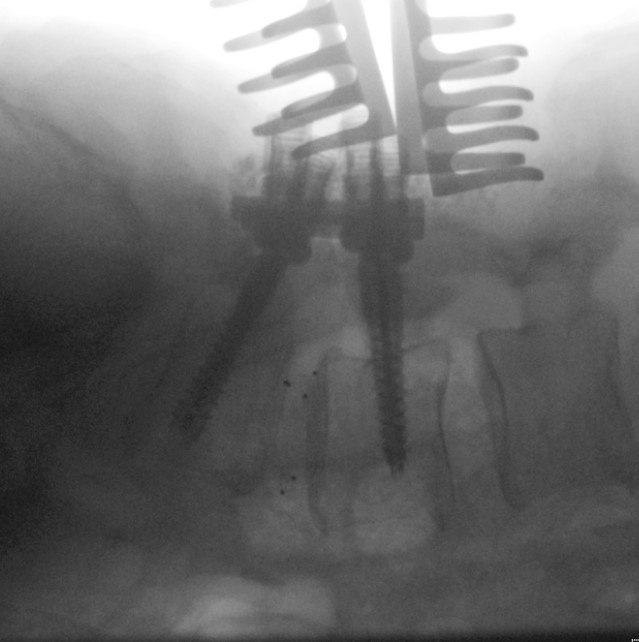

| final.png | 2025-12-14 16:21 | 322K | ||

| placing-screw-in-L4.png | 2025-12-14 16:21 | 363K | ||

| placing-screw-in-L5.png | 2025-12-14 16:21 | 361K | ||